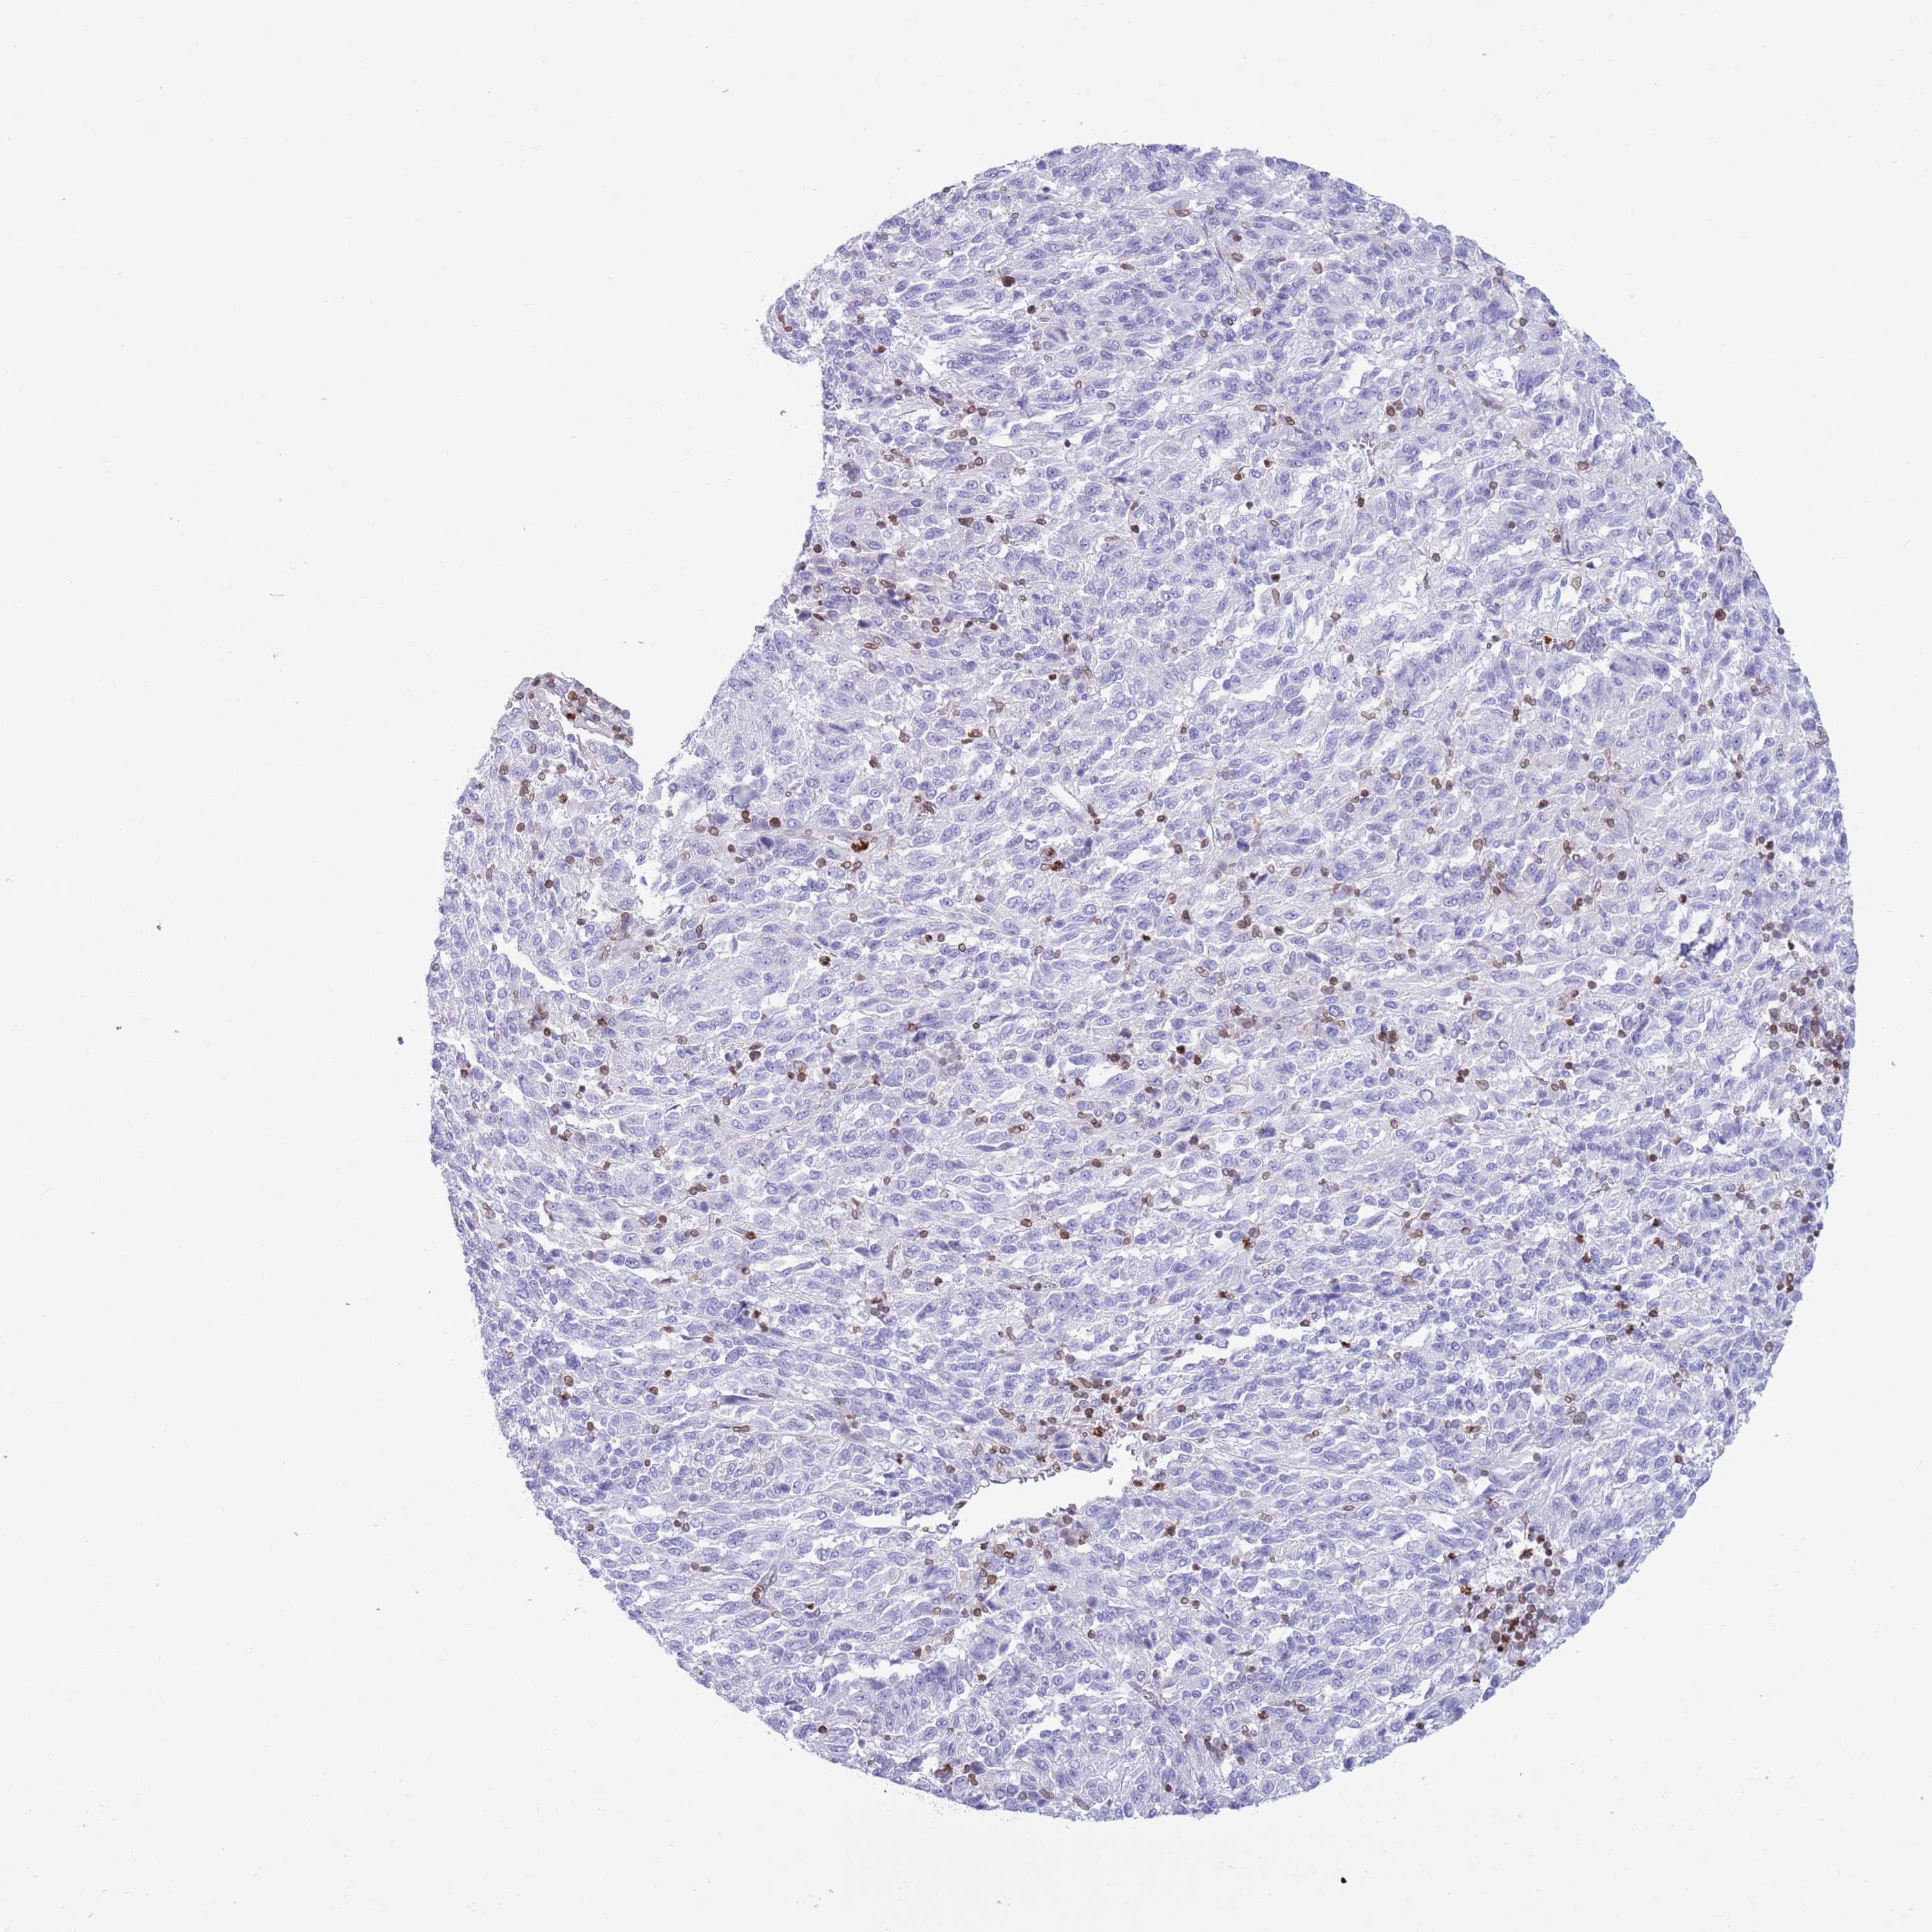

MELANOMA - Protein expressioni

A mouse-over function shows sample information and annotation data. Click on an image to view it in a full screen mode. Samples can be filtered based on level of antibody staining by selecting one or several of the following categories: high, medium, low and not detected. The assay and annotation is described here.

Note that samples used for immunohistochemistry by the Human Protein Atlas do not correspond to samples in the TCGA dataset.

Antibody stainingi

Antibody staining in the annotated cell types in the current human tissue is reported as not detected, low, medium, or high, based on conventional immunohistochemistry profiling in selected tissues. This score is based on the combination of the staining intensity and fraction of stained cells.

Each image is clickable and will lead to virtual microscopy that enables deeper exploration of all samples and also displays staining intensity scores, fraction scores and subcellular localization as well as patient and tissue information for each sample.

Antibody HPA049840

Antibody HPA062236

Staining

High

Medium

Low

Not detected

Intensity

Strong

Moderate

Weak

Negative

Quantity

>75%

75%-25%

<25%

None

Location

Nuclear

Cytoplasmic/membranous

Cytoplasmic/membranous,nuclear

Malignant melanoma, NOS

Malignant melanoma, Metastatic site